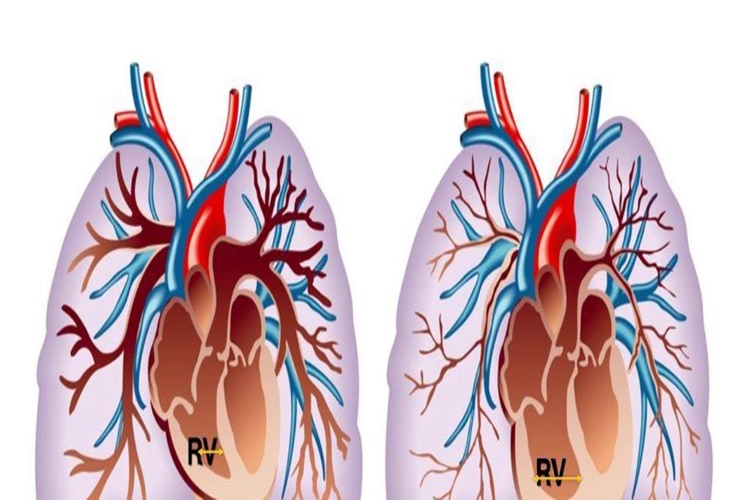

Böbrekler Az Çalışırsa Ne Olur?

Böbrekler gerektiği gibi çalışmadığı taktirde insan

vücudunda aşırı potasyum birikmesi yaşanmaktadır. Bu da kemiklerden kalsiyum

çekilmesine sebebiyet verecektir. Çalışmayan böbrekler aynı zamanda D

vitamininin kullanımında sorunlara neden olabilmektedir. Her iki durumda

sağlıksız kemiklere ve kolay kemik kırılmalarına sebep olabilir.

Böbrek yetmezliğine bağlı sırt ağrısı, hasta hissi, kusma,

yüksek vücut ısısı ve sık idrara çıkma durumları gözlemlenir. Normal sırt

ağrısı böbreklerle hiçbir korelasyon göstermeyecektir. Böbreklerde ağrı daha

lokalizedir ve aniden olur, ateş olmaz. Sırt ağrısı yaşıyorsanız ve ağrı kesici

haplar etkisiz ise hekime danışmak önerilmektedir.